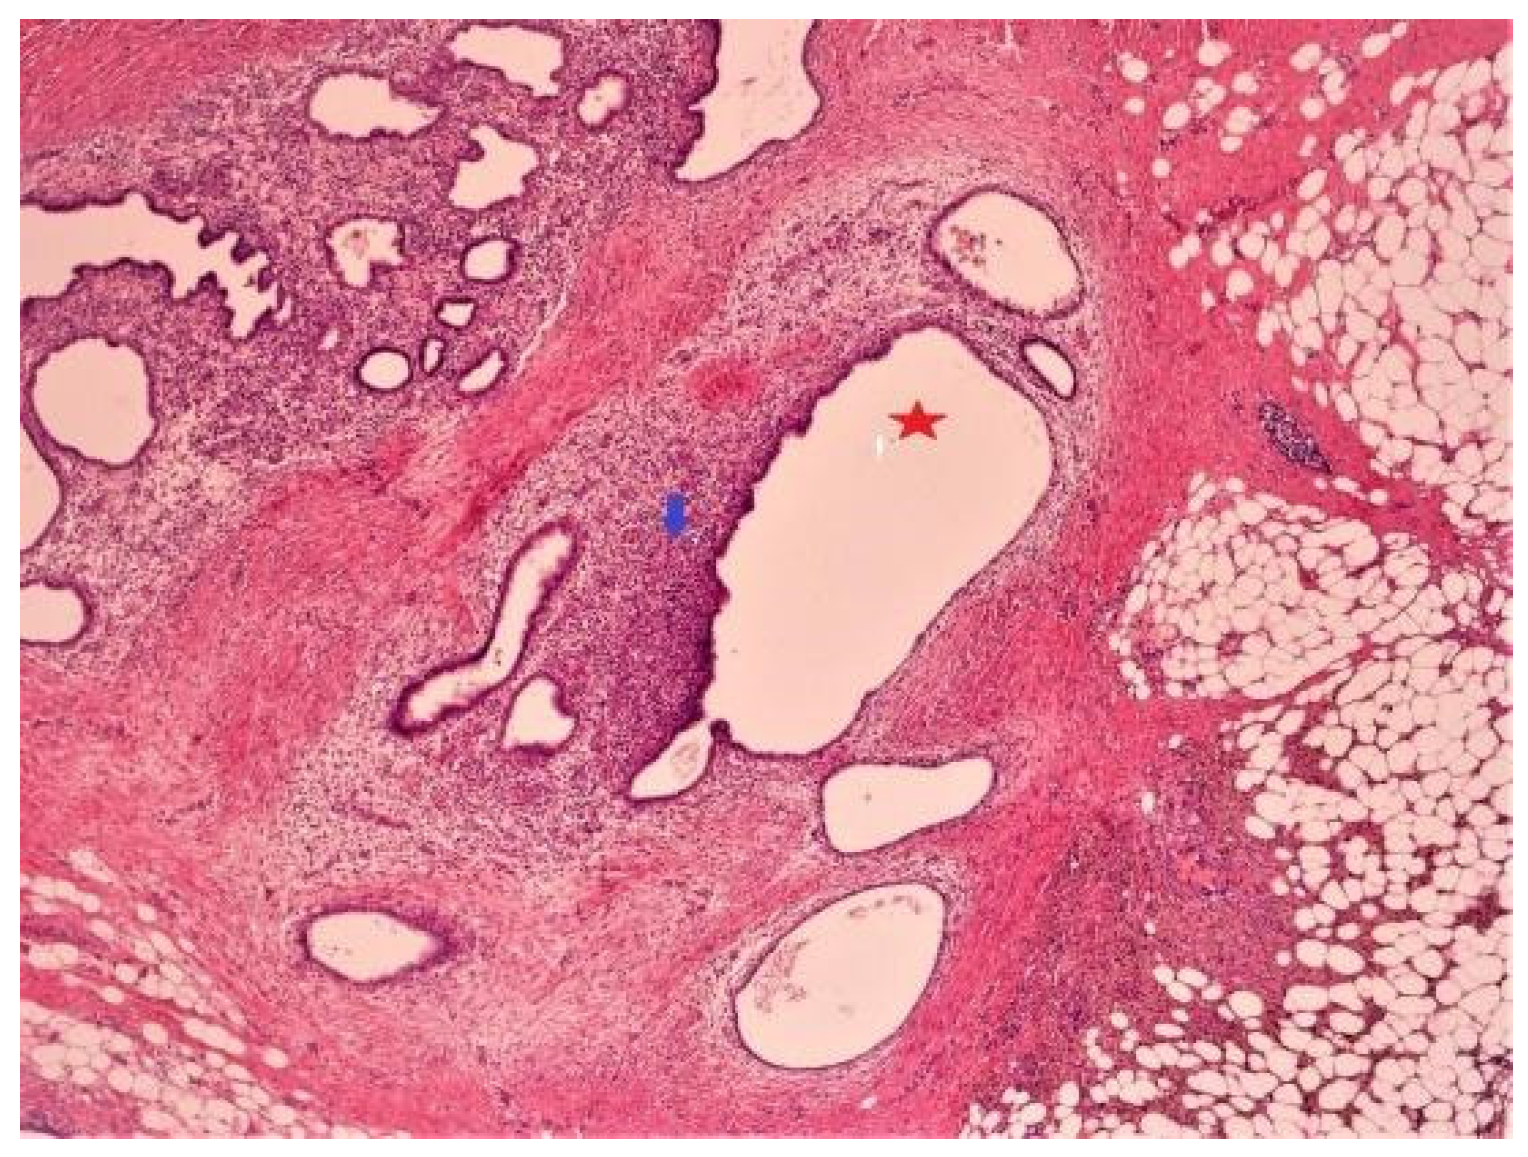

Histopathological Examination Results